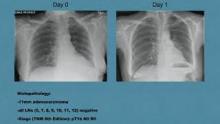

The authors present the case of a 63-year-old patient with an 11 mm nodule in the posterobasal segment (S10) of the left lower lobe. This grew from an initial size of 8 mm over a 12-month period. Image-guided biopsy was rejected, and after a multidisciplinary meeting discussion and with further discussion with the patient, a segmentectomy for diagnosis and potential treatment was planned. The tumor location and the lung anatomy on the CT scan were carefully reviewed and a combined S9+S10 bisegmentectomy was planned.